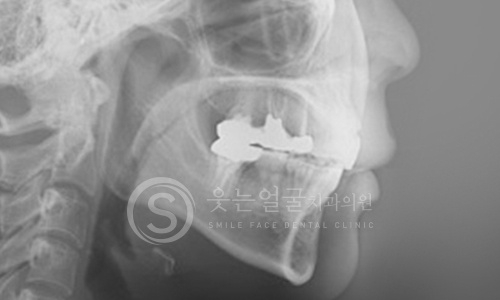

웃는얼굴치과의 12단계 교정진단시스템은 환자의 치아와 턱 구조,

얼굴 균형, 교합 상태 등을 체계적으로 분석하여

최적의 치료 계획을 수립하는 첨단 진단 프로세스입니다.

02 파노라마 촬영

03 세팔로 촬영

05 정면 X-ray 촬영